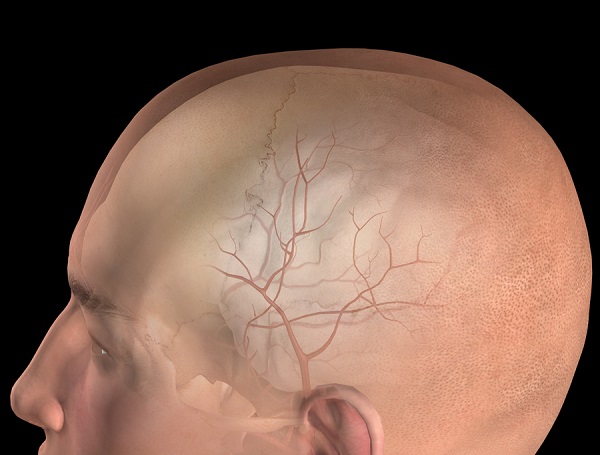

Эпидуральная

Эпидуральная гематома возникает вследствие травмы головы, однако в данном случае происходит вдавливание костей черепа, что и объясняет локализацию кровоподтека. В отличие от субдуральной она практически всегда образовывается в месте удара, а не с противоположной стороны.

Как правило, гематома образуется вследствие кровотечения из средней менингеальной артерии (в большинстве случаев) или из передней решетчатой атерии, поэтому локализация отмечается в височной и лобной долях головного мозга. Кровь же скапливается между черепной коробкой и твердой мозговой оболочкой.

Объем скапливающейся крови, в среднем составляет от 40 до 200 мл, диаметр, как правило – 7-8 мм.